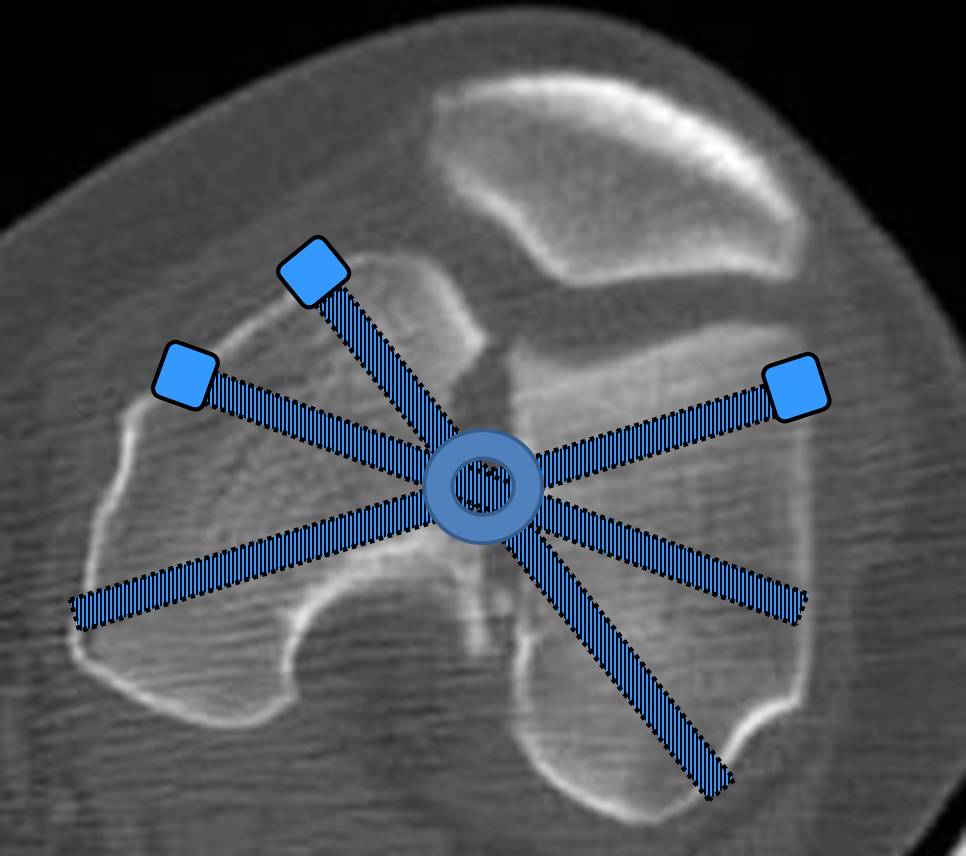

С моей точки зрения, безусловная ценность  предложенного Вами, Александр Николаевич, стержня состоит в возможности введения блокирующих винтов максимально близко к суставной поверхности дистального отломка, что значительно расширяет показания для применения интерлокинга. Можно предположить, что  в техническом плане  таким образом ввести блокирующие винты является непростой задачей. Кроме того,  все они расположены в одной плоскости на небольшом расстоянии друг от друга. Мне представляется, что конструкция с максимальными прочностными характеристиками будет иметь вид предложенной во вложенном файле. Такую конфигурацию расположения блокирующих отверстий на дистальном конце имеет стержень для большеберцовой кости фирмы ChM. Для бедренной кости такой стержень мне неизвестен. Поэтому в необходимых случаях (хорошо, что такие случаи встречаются не часто), как вариант, мы используем  custom made стержень.

Имя     : locking.jpg